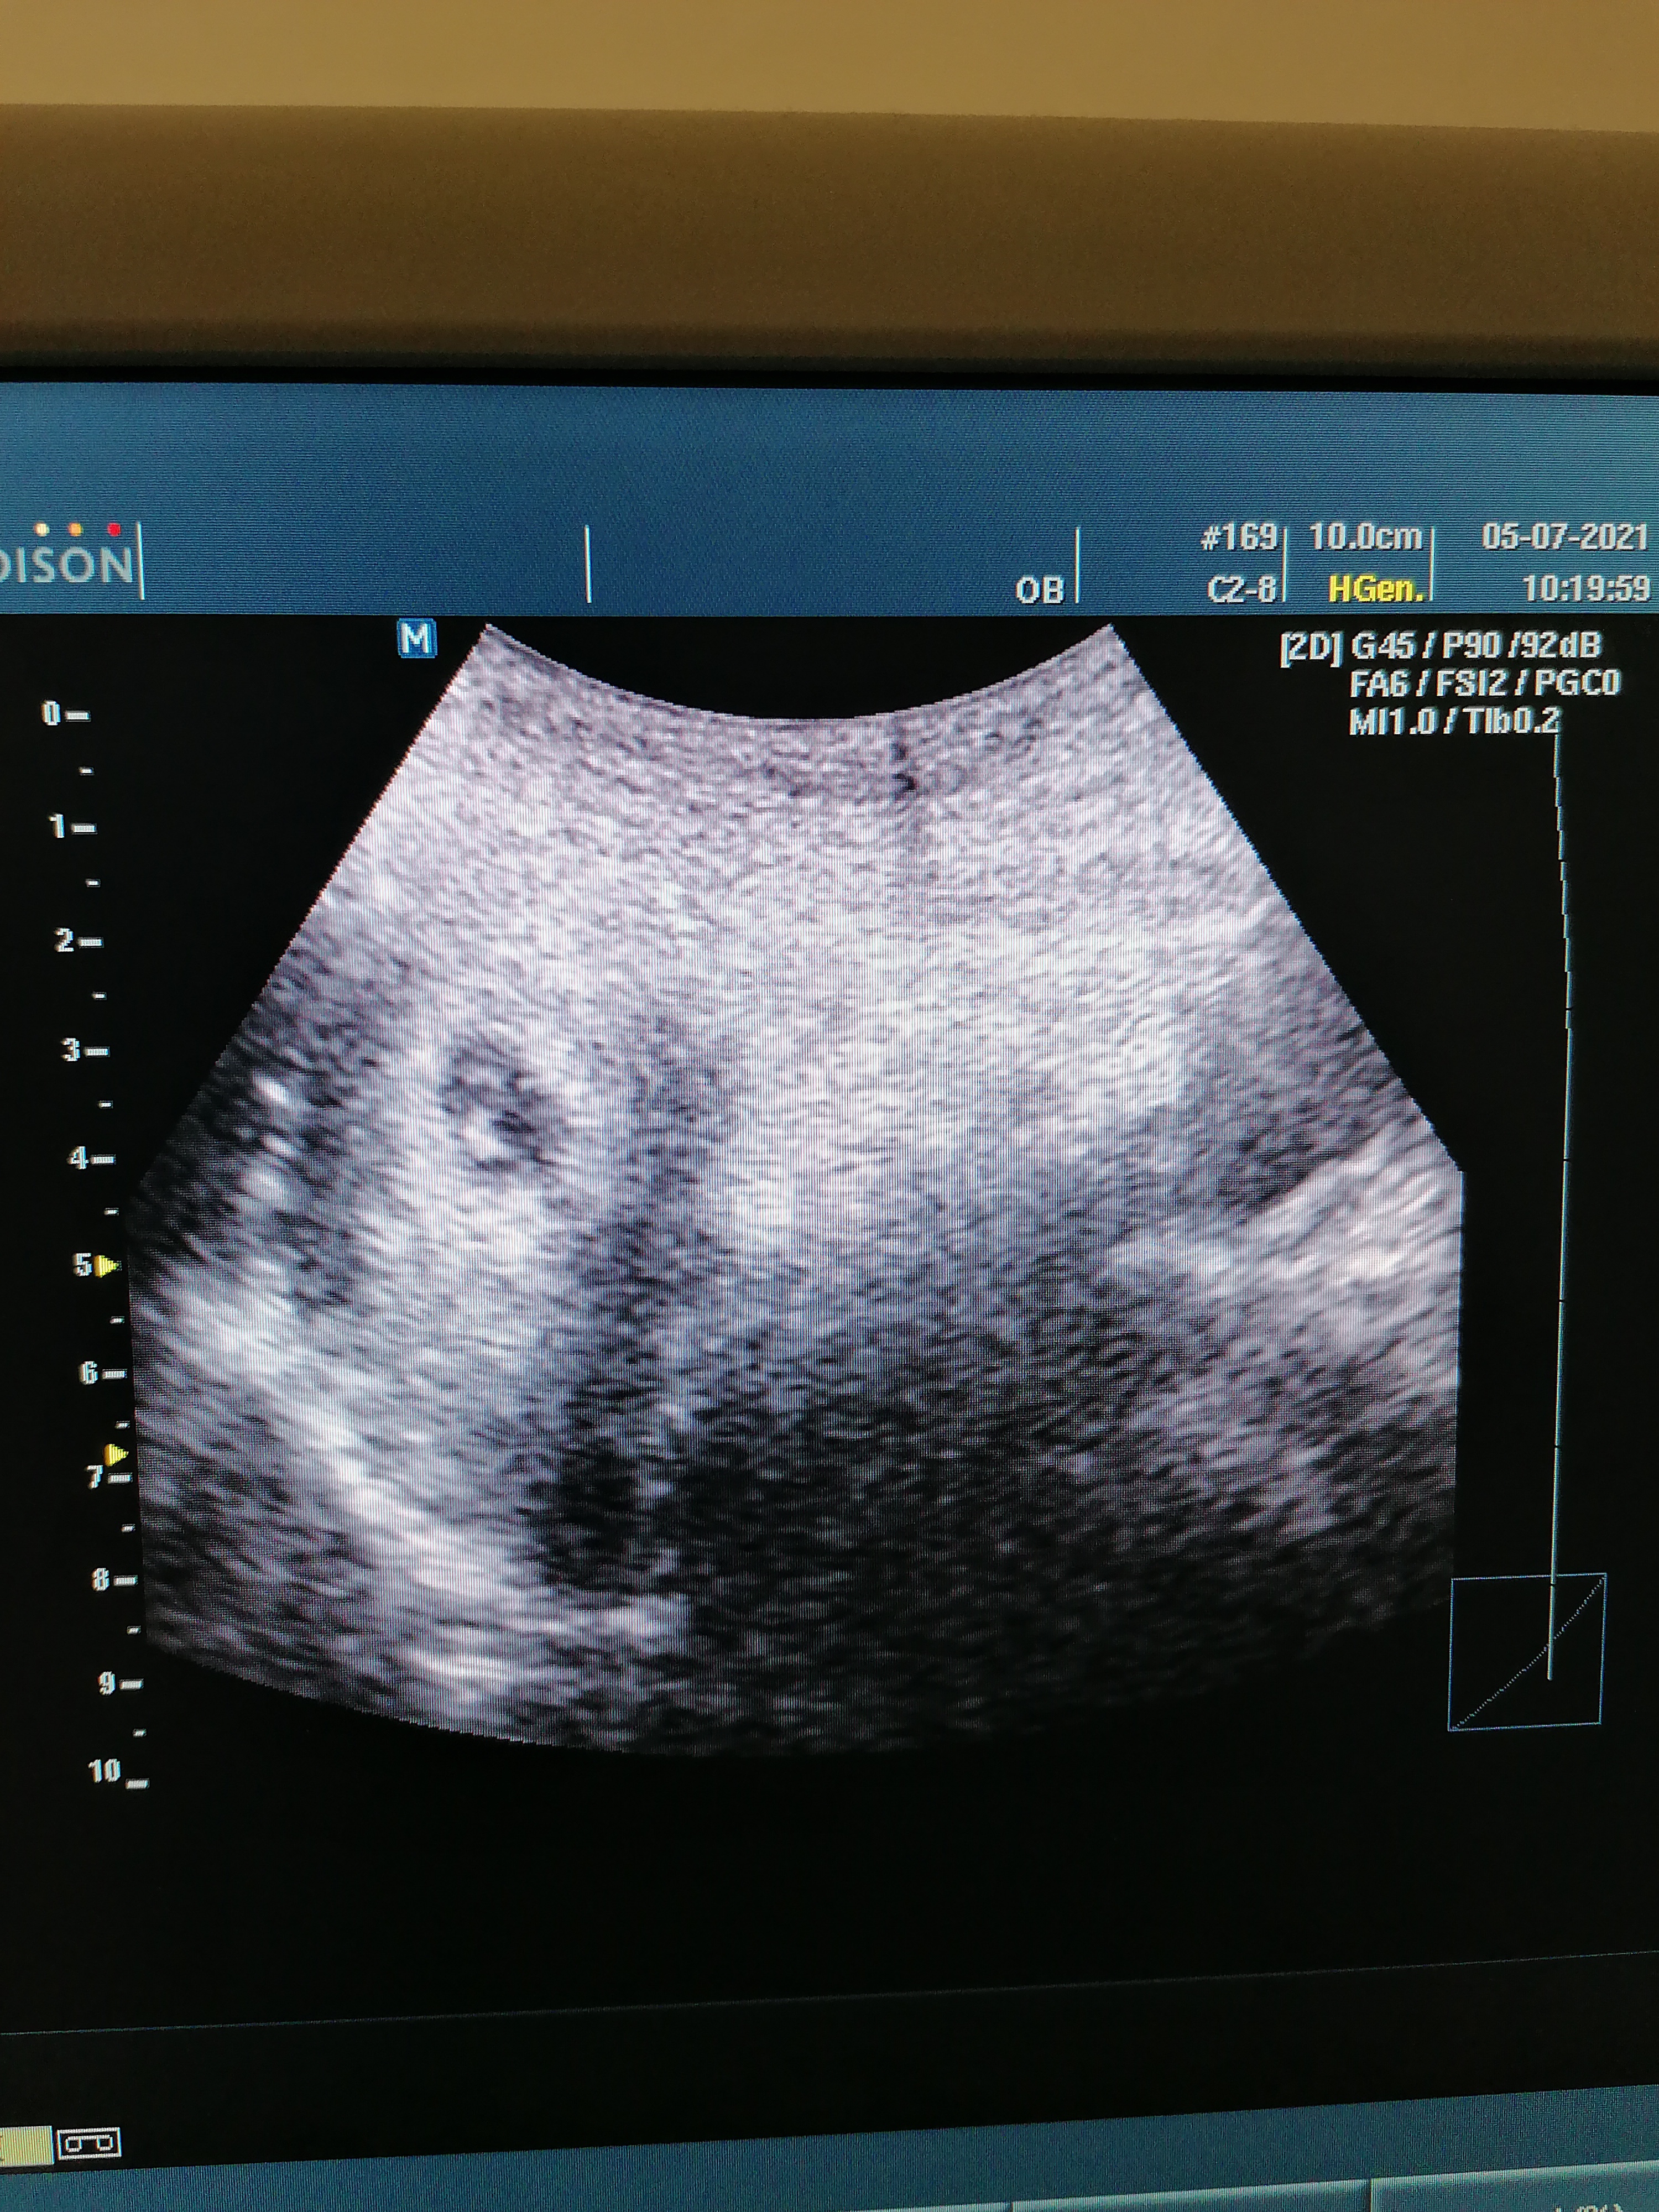

Kızlar bu keseyi ben neden göremiyorum acaba doktor çok ilgisiz ve tersti malesef bıdaha gitmem zaten yardımcı olurmusunuz